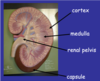

Label this cross section of the kidney…